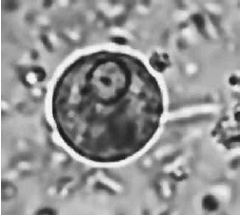

O diagnóstico laboratorial de algumas doenças infecciosas que acometem o trato gastrointestinal é realizado por meio do exame parasitológico de fezes.

A imagem ilustra o achado de um exame parasitológico de fezes de um paciente cujo diagnóstico é de doença causada pelo seguinte agente etiológico: